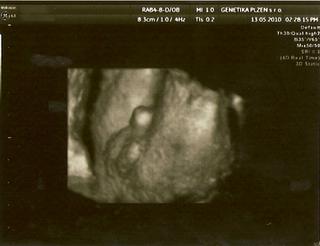

Dneska jsem byla znovu na tom 3D UTZ a miláček náš maličkej (zase tak maličkej není, dle MS 27+6 ale dle UTZ 29+0 a odhad váhy 1300g 😵 ) úžasně spolupracoval, takže teď jdu naskenovat fotečky a za chvíli vám je ukážu 😵

tak naskenováno 😵

Tak ty fotky jsou absolutně boží!!!!

Micha, fotečky Vojtíška jsou naprosto úžasné 🙂 Moc mu to sluší... To byl zážitek, co?